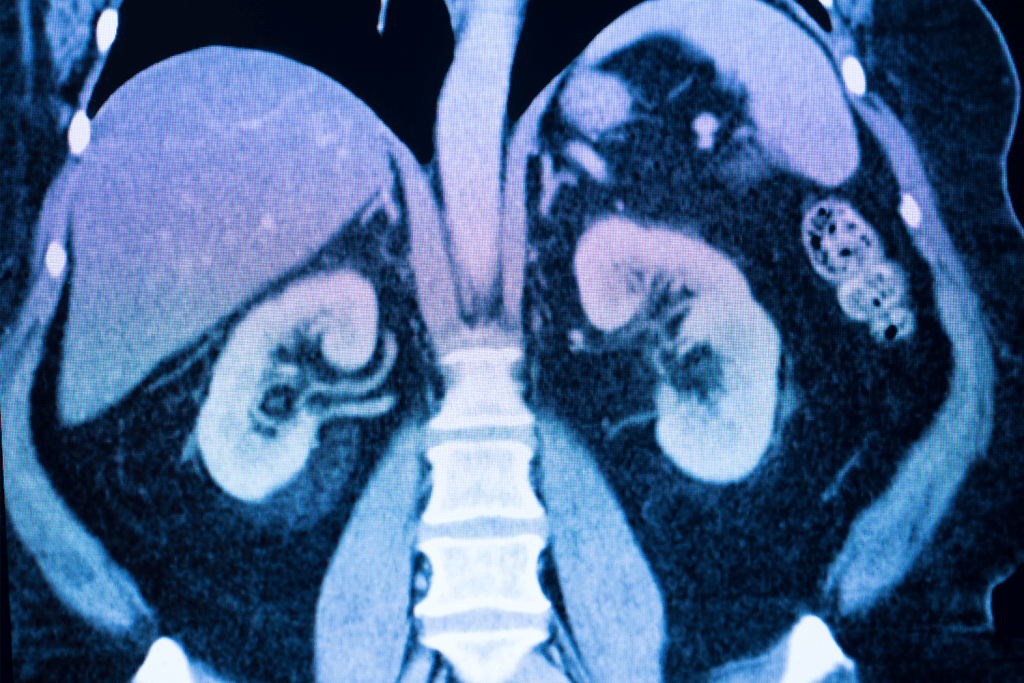

A kidney MRI is a noninvasive test that shows detailed images of the kidneys. It helps find many kidney problems. The time it takes for a renal MRI scan can change, but it usually lasts between 30 and 60 minutes.

MRI scans of the kidneys give a detailed look at the kidneys’ structure and any problems. They help doctors make accurate diagnoses and plan treatments. This method is great for showing how the kidneys work and any issues they might have.

Detailed Imaging of Kidney Structure and Function

Kidney MRI scans take high-quality pictures of the kidneys. Doctors can see how they look and work. This is ketoor spotting problems and understanding how serious they are.